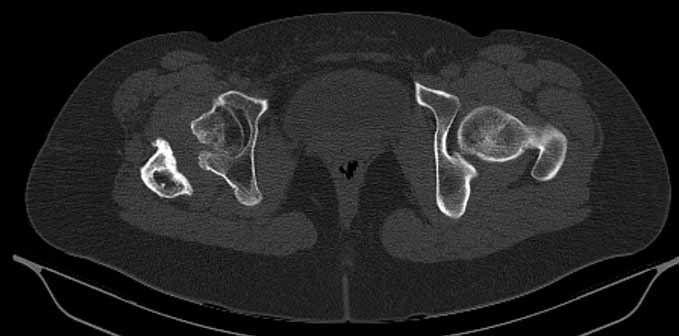

Сделал ей КТ.

С удивлением узнала, что перелом в области шейки у неё не сросся, хотя на рентгенограмме тех лет так оно и есть.

КТ - во вложении.

Интересна функциональная адаптация - практически полная функция того, что раньше было тазобедренным суставом.